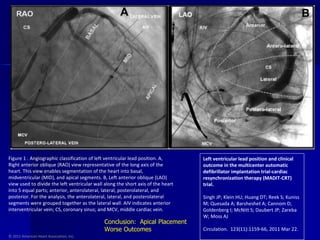

© 2011 American Heart Association, Inc. Left ventricular lead position and clinical outcome in the multicenter automatic defibrillator implantation trial-cardiac resynchronization therapy (MADIT-CRT) trial. Singh JP; Klein HU; Huang DT; Reek S; Kuniss M; Quesada A; Barsheshet A; Cannom D; Goldenberg I; McNitt S; Daubert JP; Zareba W; Moss AJ Circulation.  123(11):1159-66, 2011 Mar 22. Figure 1 . Angiographic classification of left ventricular lead position. A, Right anterior oblique (RAO) view representative of the long axis of the heart. This view enables segmentation of the heart into basal, midventricular (MID), and apical segments. B, Left anterior oblique (LAO) view used to divide the left ventricular wall along the short axis of the heart into 5 equal parts; anterior, anterolateral, lateral, posterolateral, and posterior. For the analysis, the anterolateral, lateral, and posterolateral segments were grouped together as the lateral wall. AIV indicates anterior interventricular vein; CS, coronary sinus; and MCV, middle cardiac vein. Conclusion:  Apical Placement Worse Outcomes

© 2011 AmericanHeart Association, Inc. Left ventricular lead position and clinical outcome in the multicenter automatic defibrillator implantation trial-cardiac resynchronization therapy (MADIT-CRT) trial. Singh JP; Klein HU; Huang DT; Reek S; Kuniss M; Quesada A; Barsheshet A; Cannom D; Goldenberg I; McNitt S; Daubert JP; Zareba W; Moss AJ Circulation. 123(11):1159-66, 2011 Mar 22. Figure 1 . Angiographic classification of left ventricular lead position. A, Right anterior oblique (RAO) view representative of the long axis of the heart. This view enables segmentation of the heart into basal, midventricular (MID), and apical segments. B, Left anterior oblique (LAO) view used to divide the left ventricular wall along the short axis of the heart into 5 equal parts; anterior, anterolateral, lateral, posterolateral, and posterior. For the analysis, the anterolateral, lateral, and posterolateral segments were grouped together as the lateral wall. AIV indicates anterior interventricular vein; CS, coronary sinus; and MCV, middle cardiac vein. Conclusion: Apical Placement Worse Outcomes